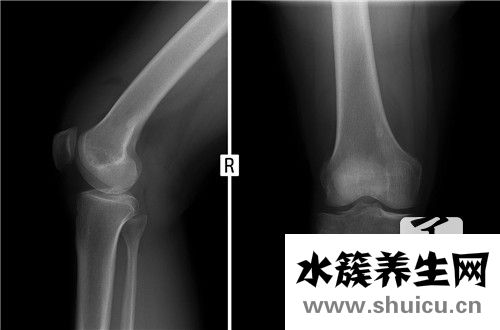

封閉式治療是一種很好的治療方法。絕大多數人可以通過這種治療得到緩解。臨床上比較常用的閉合性治療疾病有腱鞘炎、肩周炎、骨性關節炎、網球肘、足跟疼痛等。,因為這些疾病大部分都是局部無菌炎癥引起的疼痛,所以在局部注射激素和麻醉藥品的混合水溶液中,由于激素具有很強的抗炎作用,而麻醉藥品具有很快的鎮痛作用,所以封閉針頭是以局部形式出現的,具有較強的抗炎鎮痛作用。